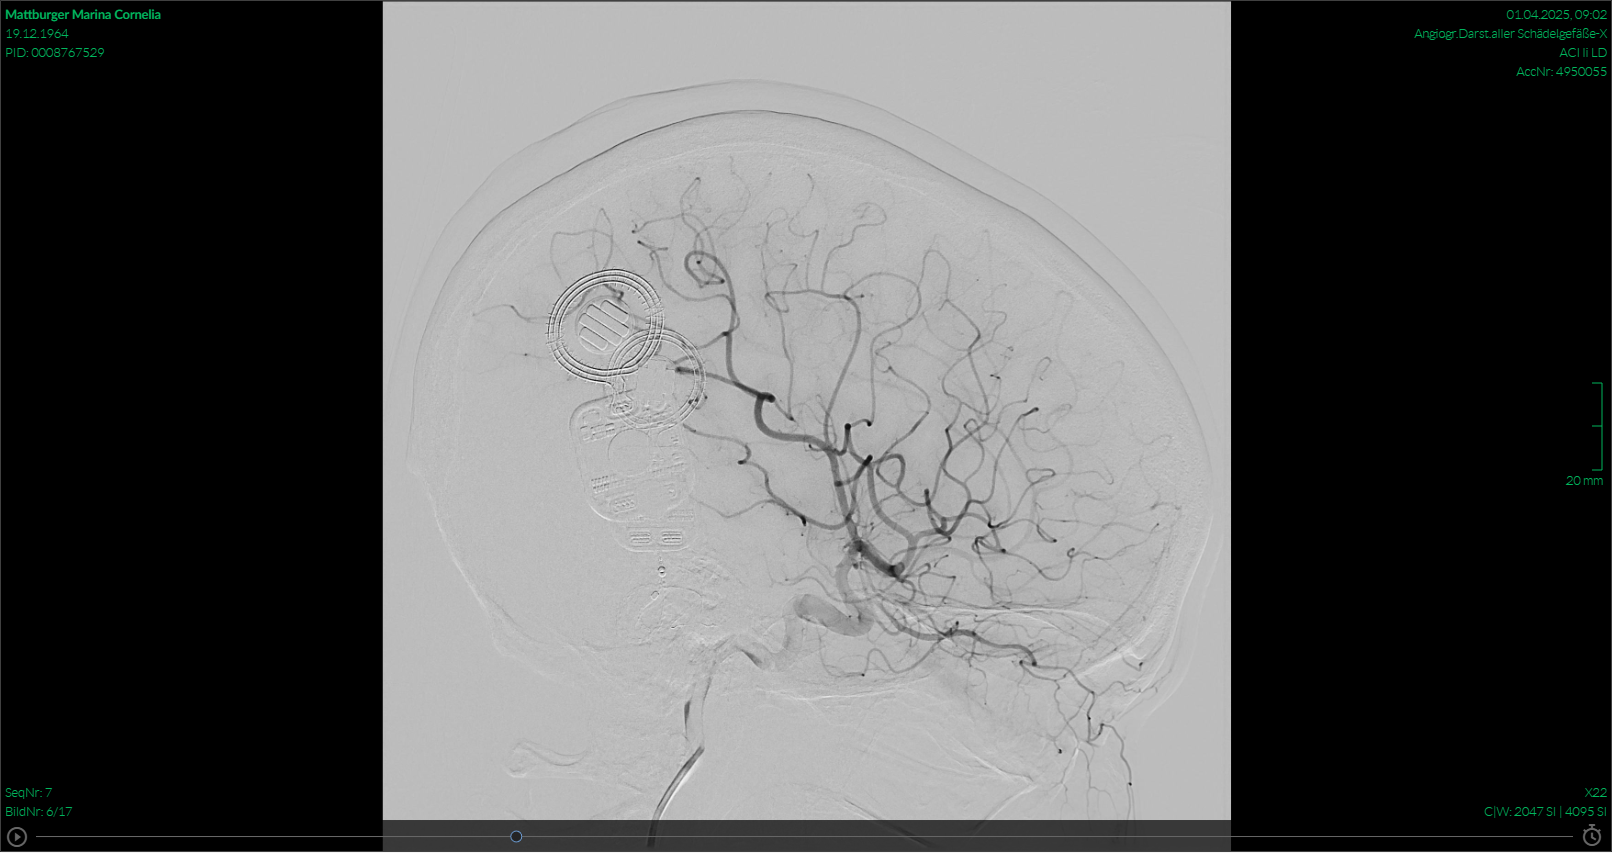

Am nächsten Tag wurde ich zum MRT gebracht, der Arzt hat sich mit Tübingen kurzgeschlossen und, da ich ja meine Ausweise der Implantate dabeihatte, grünes Licht für das MRT erhalten. Bedingt durch die CIs hat man auf den Bildern auch nicht wirklich was sehen können. Was mir schon klar war, im Nachhinein war auch wirklich nix zu sehen.

Es geht mir wieder gut, das ist die Hauptsache. Die Bilder zeigen Aufnahmen vom MRT und von der Subtraktionsangiographie. Ich hoffe, ich mache euch ein wenig Mut, keine Angst vor solchen Untersuchungen zu haben. Auch mit CI geht das!